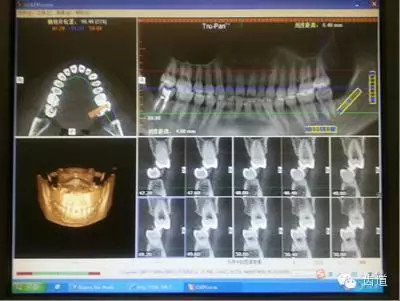

病例二:(權(quán)老師會(huì)診病例圖2、圖3)患者,女,24歲。主訴:左側(cè)顳下頜關(guān)節(jié)區(qū)張口疼痛,打哈欠時(shí)疼痛更明顯。從以下CBCT截圖中,我們能讀出哪些信息?

圖2

多位醫(yī)生均發(fā)現(xiàn):

左7正鎖合,47根管治療,中線不齊,切端對(duì)刃,下前牙扭,下前牙牙根吸收等問(wèn)題。同時(shí)也提出一些疑問(wèn):前伸(牙合)是否有異常,髁突是否對(duì)稱(chēng),關(guān)節(jié)盤(pán)的位置是否正常等。

權(quán)老師指出:

通過(guò)CT和臨床檢查,患者覆蓋和覆(牙合)不足;開(kāi)口度尚可,開(kāi)口型呈“Z”型軌跡;左側(cè)咬肌區(qū)有輕微壓痛,無(wú)明顯彈響和其他雜音;髁突疑似吸收,升支似乎變短。初步診斷正鎖合是引起同側(cè)TMJ疼痛的原因。雖然信息有限,但我們依然可以從中學(xué)習(xí)到東西,用(牙合)學(xué)的思維去驗(yàn)證和排除我們的疑問(wèn)和猜想。